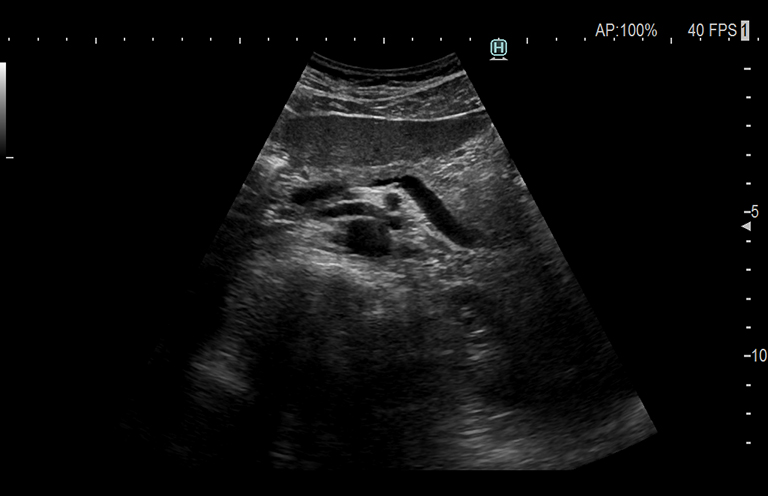

Aplicación: Abdomen

Función/análisis: Modo B

Comentarios: Páncreas